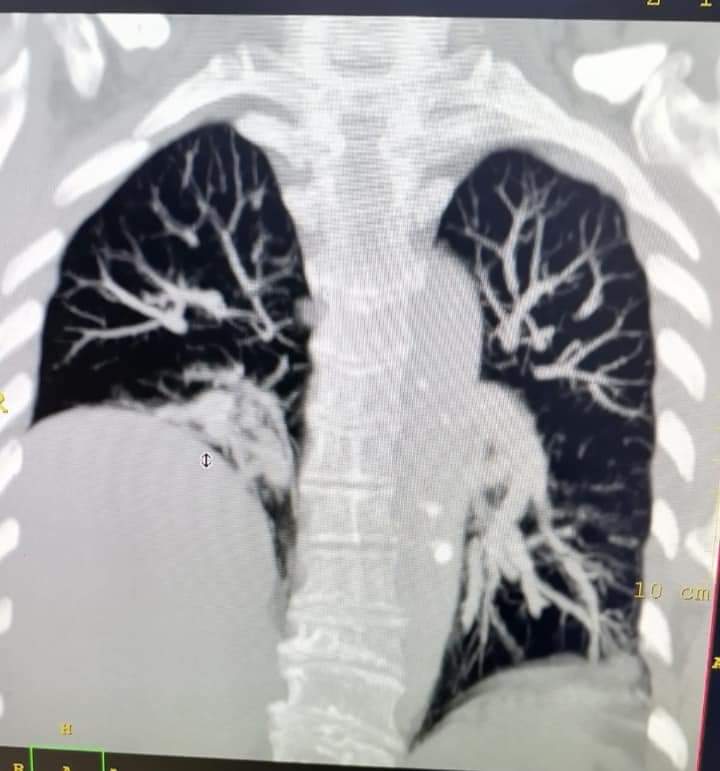

فحص رنين مغناطيسي البطن والحوض